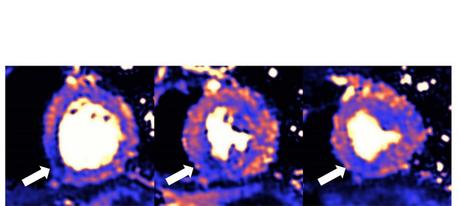

Ces lésions cardiaques retrouvées chez plus de la moitié des patients atteints de COVID-19 sévères, sortis de l'hôpital, restent détectables par imagerie par résonance magnétique (IRM) au moins un mois après la sortie, selon cette étude menée à l’University College London(UCL) publiée dans l'European Heart Journal. Les dommages ici documentés comprennent l'inflammation du muscle cardiaque (myocardite), la cicatrisation ou la mort du tissu cardiaque (infarctus), la restriction de l'apport sanguin au cœur (ischémie : Voir visuel)- et la combinaison de ces 3 conditions.

- la lésion tissulaire semble provenir d'une inflammation chez 26% des patients, d'une cardiopathie ischémique (infarctus ou ischémie), chez 22% des patients ou « des deux » chez 6% des patients. 8% des patients présentent une inflammation cardiaque persistante.